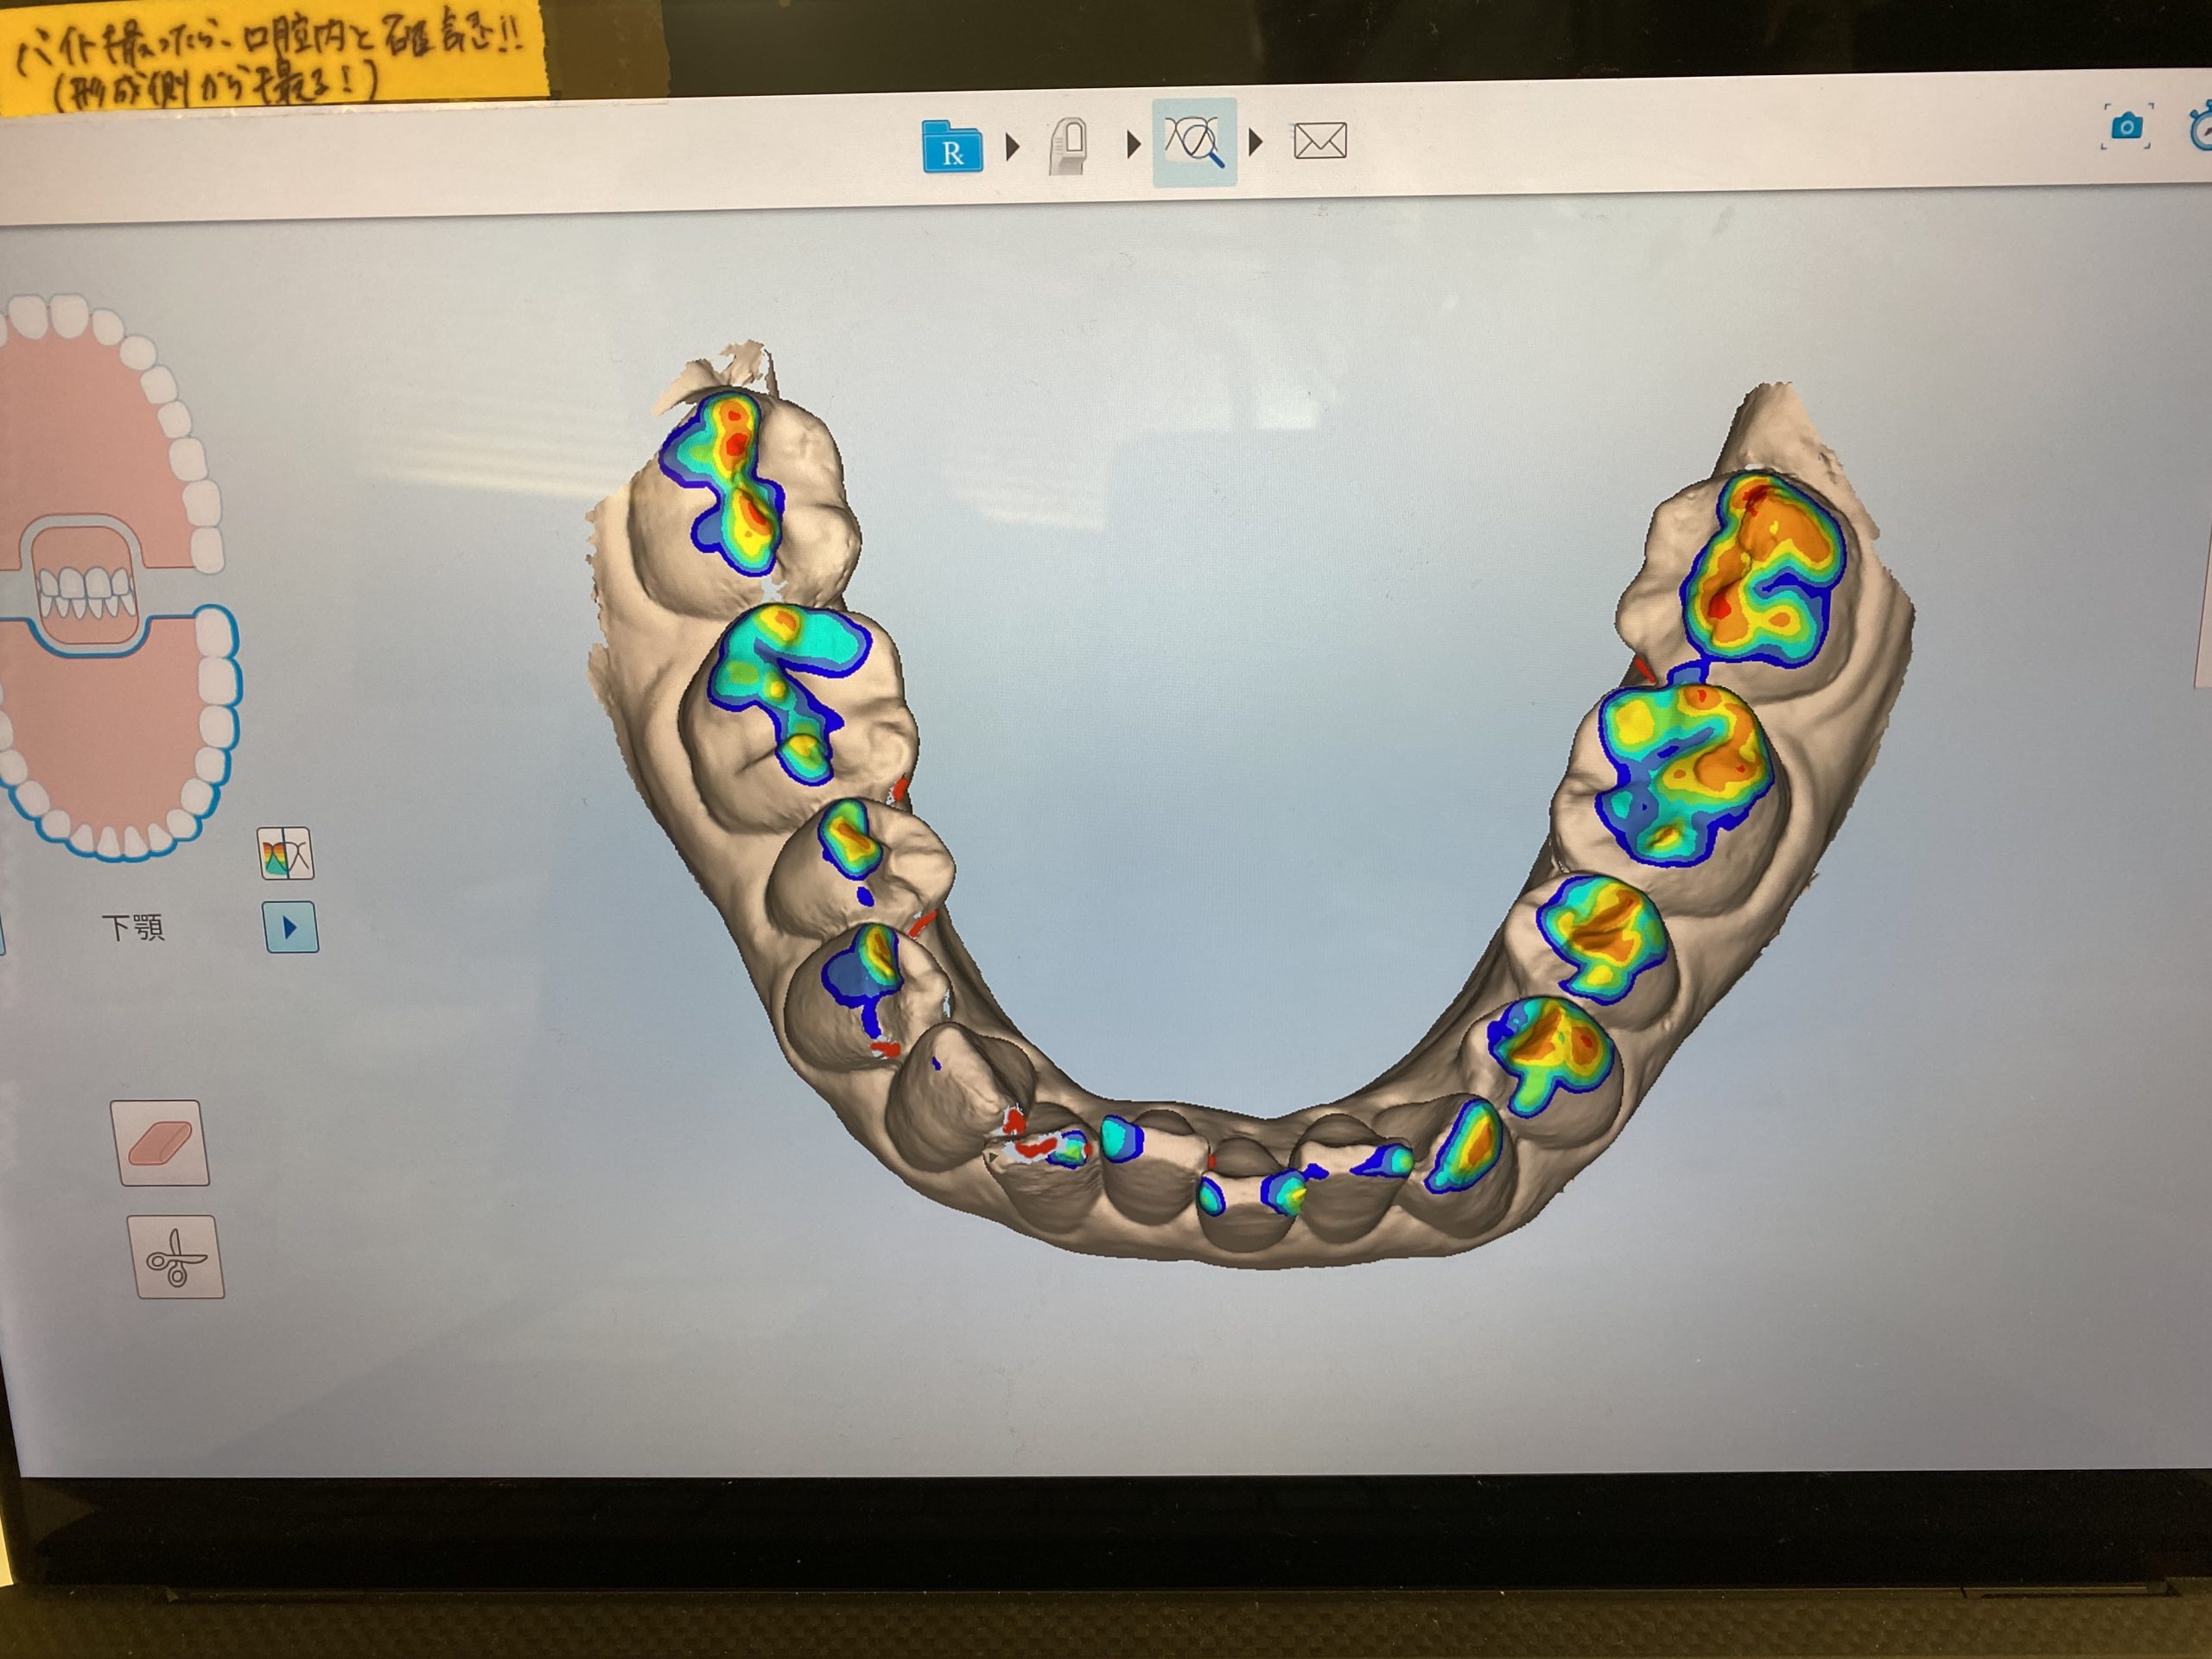

3Dスキャナーで一歩先を行く診療を実現 2022.1.1

マウスピース矯正、インビザラインの矯正装置を作製する時『iTero Element(アイテロ エレメント)』という3Dスキャナーで採取しています。

今までは『シリコン印象』という精密印象材で、型をとるため嘔吐反射がある方は特に大変でした。

この『iTero』の導入で快適にしかも精密に歯型をとることができます。

これまではシリコン印象した歯型をアメリカまで空輸していたのですが、今ではデータをインターネットで送りますので1~2週間も早く治療をスタート出来るのです。

単なる口腔内スキャナーではなく

・3Dデジタル印象、ジルコニアなどの補綴物の型取りも行います

・口腔内カラー写真

・経時的変化を記録することで患者様により理解して頂けます

・嚙み合わせの強い所、弱いところなどの咬合診断

・隣接面の虫歯の発見

・歯がどのように動いていくかのシュミレーションシステム

・もちろん口腔内カメラとしても使えますが、なんと言っても放射線照射なしなのです。

近赤外光画像(NIRI)技術で歯の内部構造をリアルタイムでスキャンしデータ化します。

普通のレントゲンでは心配という患者様に早期発見に役立ちますね。

矯正だけでなく嚙み合わせが不調の方も先進的な視覚化ツールで患者様は御自身の口腔内状態についてリアルタイムで知ることができます。

私達クリニック側からも、診断と治療のワークフローがよく患者様の石膏模型もスキャンデータでクラウド上に保管できるのも助かります。

今年もどんどん進化し続けますのでどうぞよろしくお願い致します。